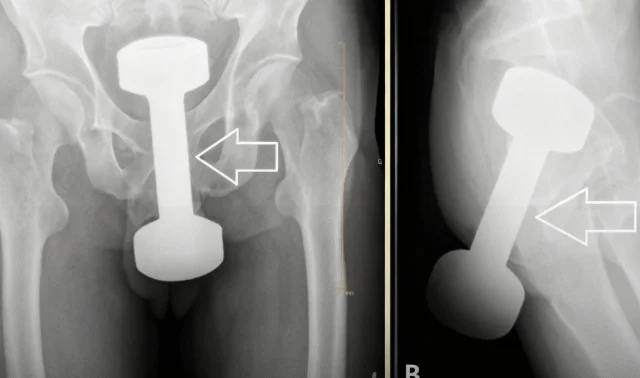

Profissionais de saúde viveram uma situação fora do comum quando um homem procurou atendimento reclamando de dor intensa na região abdominal e dificuldade para evacuar. Os exames revelaram um cenário improvável: um halter de 2,5 kg estava completamente introduzido no reto do paciente.

Objeto de academia foi identificado por exames após o homem relatar dor intensa; retirada precisou de técnica especializada/Foto: Reprodução

A retirada do item exigiu um procedimento minucioso para evitar lesões graves no intestino, dada a rigidez e o peso do objeto. A operação foi bem-sucedida, e o paciente não sofreu sequelas, mas se recusou a contar como tudo aconteceu, deixando mistério no ar.